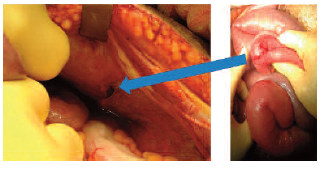

Initially, he was treated with nil by mouth, intravenous fluid, and antimicrobial agents; however, overnight his symptoms worsened with increased pain, abdominal distention, and decreased bowel sounds. An abdominal radiograph showed dilatation of the small bowel, suggestive of an obstruction (Figure 1). An axial computed tomographic scan of the abdomen showed distention of the small bowel with a transition point in the left lower quadrant above the transplanted kidney (Figure 2). The patient underwent an exploratory laparotomy, reduction of the small bowel loop (which was distended but still viable), entrapped through a defect in the peritoneum covering the transplanted kidney (Figure 3). He did not require a bowel resection, and the peritoneal defect was closed with absorbable sutures. His recovery was uneventful.

Figure 3. Exploratory Laparotomy Resulting in a Reduction of a Small Bowel Loop (Right Side), Entrapped Through a Small Defect (2 cm) in the Peritoneum (Arrow) Covering the Transplanted Kidney